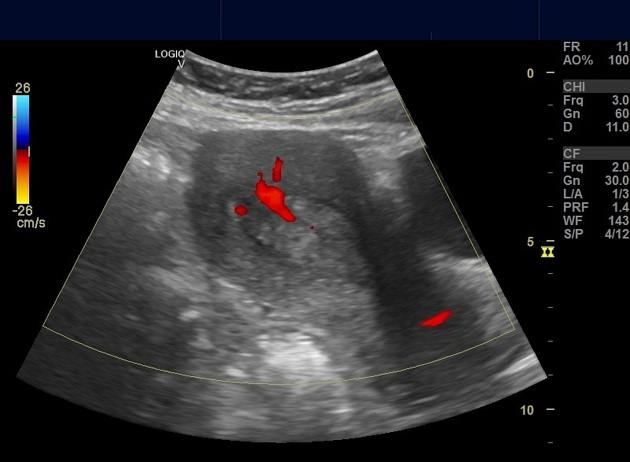

Polyp nội mạc tử cung

» Thông tin: Nữ giới – 40 tuổi.

» Lâm sàng: Rong kinh.